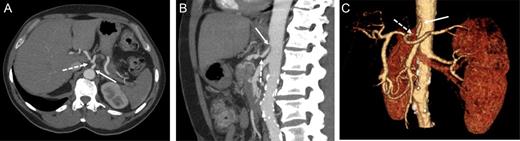

At this point, the patient was recommended for further investigation in the Interventional Radiological Department for both diagnosis confirmation and, most importantly, to provide an opportunity for stenting the celiac trunk. In order to accomplish this, gastro-duodenostomy, choledoco-choledocostomy (anastomosis between the resected common bile duct) and jejuno-jejunostomy re-anastomosis were performed, and a temporary abdominal closure was done. The patient was taken to the Radiological Department. CT and angiography (Figs 2 and 3) showed that there was a narrowing part of the celiac trunk, and distal to this part, there was an occlusion (high degree of stenosis) of the celiac artery. In addition, retrograde filling of the GDA could be appreciated through the patent SMA (Fig. 3). A stent was considered impossible due to the high degree of stenosis that was a nearly total occlusion of the celiac trunk.

Contrast-enhanced CT in the arterial phase: axial (A) and sagittal (B) maximum intensity projections (MIP), and coronal oblique 3D volume-rendered (VR) images (C) demonstrating proximal celiac artery narrowing (arrow) due to compression by the median arcuate ligament. Downstream, an additional high-degree stenosis of the celiac trunk can be appreciated (dashed arrow).